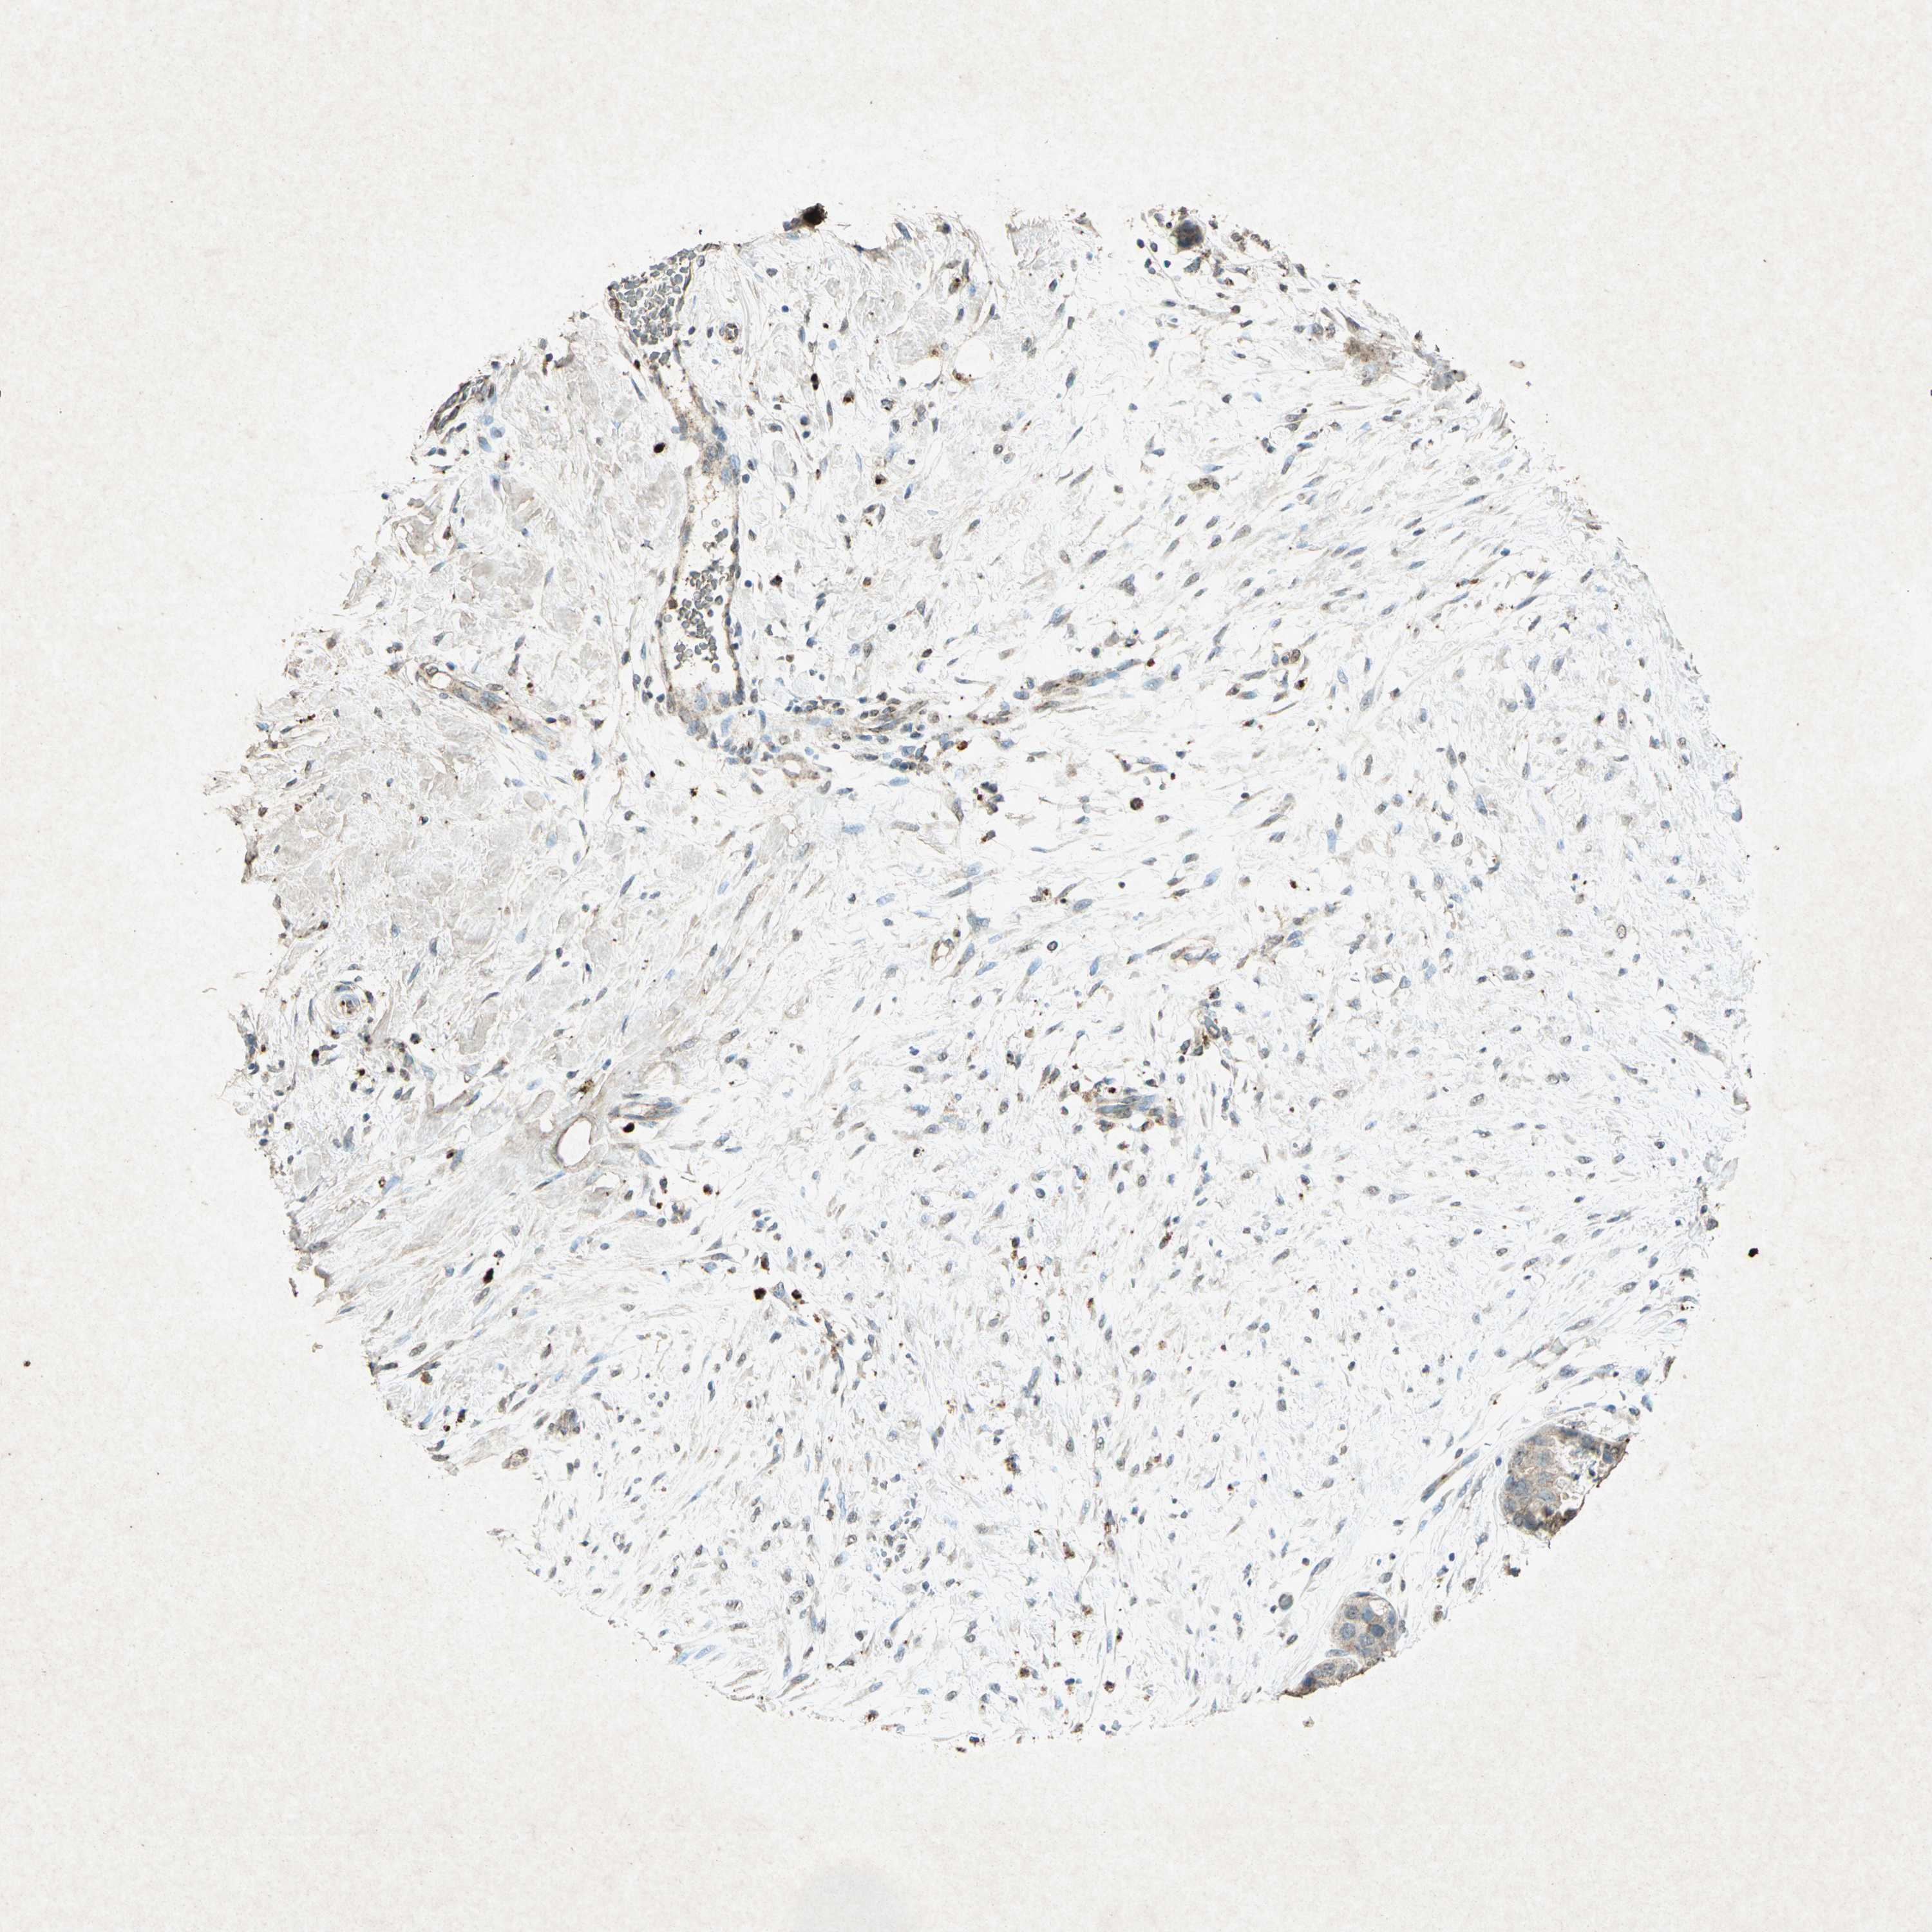

CANCER BREAST CANCER Show tissue menu

BRCA TCGA BRCA VALIDATION PROTEIN EXPRESSION

Breast cancer

Human cancer

Breast invasive carcinoma

PSEN1 is not prognostic in Breast Invasive Carcinoma (TCGA)